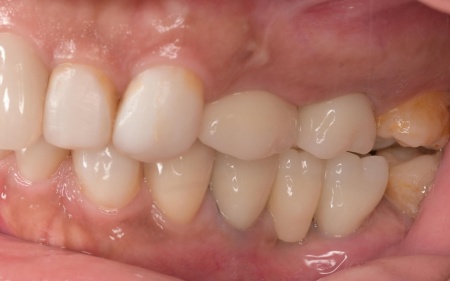

治療前

拝見したところ、もともと左上の歯と左下前歯が欠損しているうえ、奥歯の欠損も進んでいたため、噛み合わせが低くなっていました。

奥歯が噛み合わない状態になったことで、上前歯が前方に押し出され、出っ歯のようになっています。

また、下の歯は歯根だけが残る「残根」もあり、全体的に噛み合わせが不安定です。

さらに食いしばりの習慣があることから、残っている歯や顎関節に過度な負荷がかかっていると考えられます。